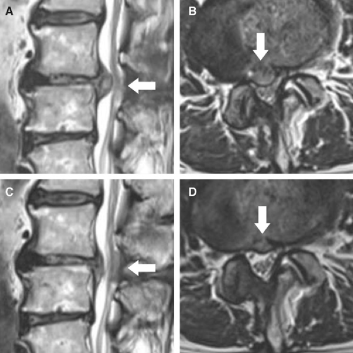

신경을 압박하는 디스크의 크기를 고주파 열응고술을 통해 감소 시키는 방법으로 급성 및 만성 디스크 병변과 척추관 협착증을 치료 합니다. 고주파 열을 이용하여 디스크의 크기를 줄일 뿐만 아니라 통증의 원인이 되는 신경을 치료하여 시술의 만족도가 높습니다.